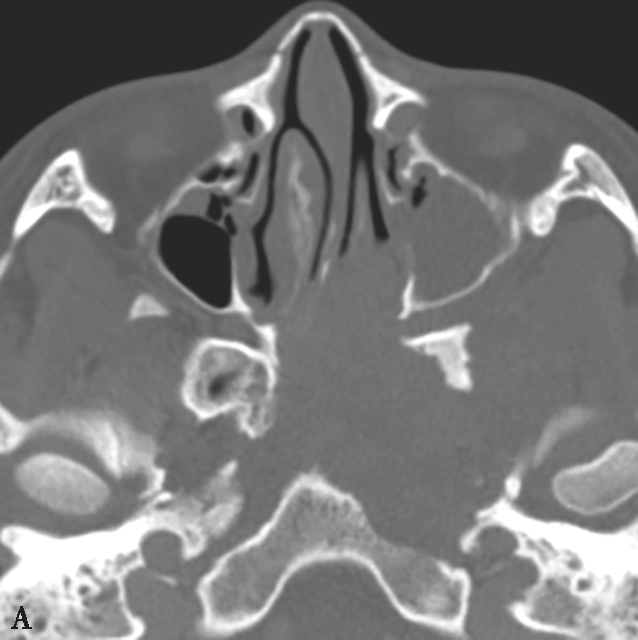

图1-2-4 青少年鼻咽纤维血管瘤

患者男,12岁,间断鼻出血1年。A.鼻窦CT横断面骨窗,示左侧蝶腭孔扩大,被不规则软组织肿块占据,病变累及左侧鼻腔、鼻咽、翼腭窝,邻近骨质可见溶骨性骨质破坏;B.鼻窦CT冠状面重组骨窗,示病变累及鼻腔、蝶窦,邻近骨质可见溶骨性骨质破坏;C.鼻咽部MR T 2 WI横断面,示左侧鼻咽、鼻腔不均匀等信号肿块,病变通过扩大蝶腭孔累及翼腭窝,病变内可见多发血管流空信号;D.鼻咽部MR T 1 WI横断面,示病变呈不均匀低信号;E.鼻咽部MR T 1 WI横断面增强+脂肪抑制序列横断面,示病变显著不均匀信号,与邻近组织分界尚清